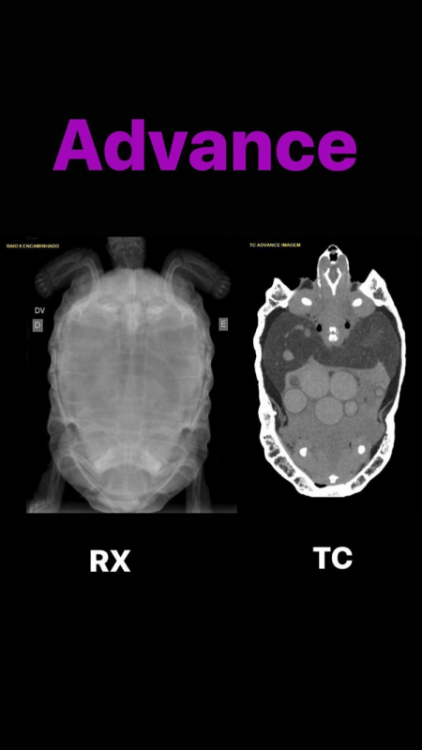

Podolnyi Ваше имя: Подольный Константин Локация: Украина, Днепр Опубликовано: 7 февраля 2020 Опубликовано: 7 февраля 2020 К примеру почему нужно очно смотреть такого рода проблемы. На фото представлен рентген черепахи и справой стороны компьютерная томография. На рентген видно, но крайне плохо, на кт, сами видите